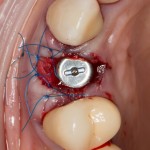

В лунку устанавливаем имплантат. В данном случае, XiVE. Длина импланта — 13 мм, диаметр 4.5 мм, подобраны, исходя из размера удаляемого зуба:

Белая штука спереди от импланта: местный препарат Neocones. Он содержит антибиотик Неомицин и анестетик Бензокаин, позволяет временно обезболить и «продезинфицировать» лунку, которая уже изначально инфицирована. Напомню, что две недели назад мы лечили периостит — гнойное воспаление поднадкостничного пространства.

На имплантат устанавливаем формирователь десны. В тот момент я думал, что ставим его временно, так как после операции в планах была коронка на имплантат:

Мы планируем восполнение отсутствующей передней стенки лунки с помощью биоматериалов, и именно для этого нужен формирователь десны. Чтобы в шахту импланта не натолкать лишнего.

Биоматериал Geistlich Bioss. В таком небольшом объеме его можно (хотя и не рекомендуется) использовать без аутокостной стружки, «вчистую»: